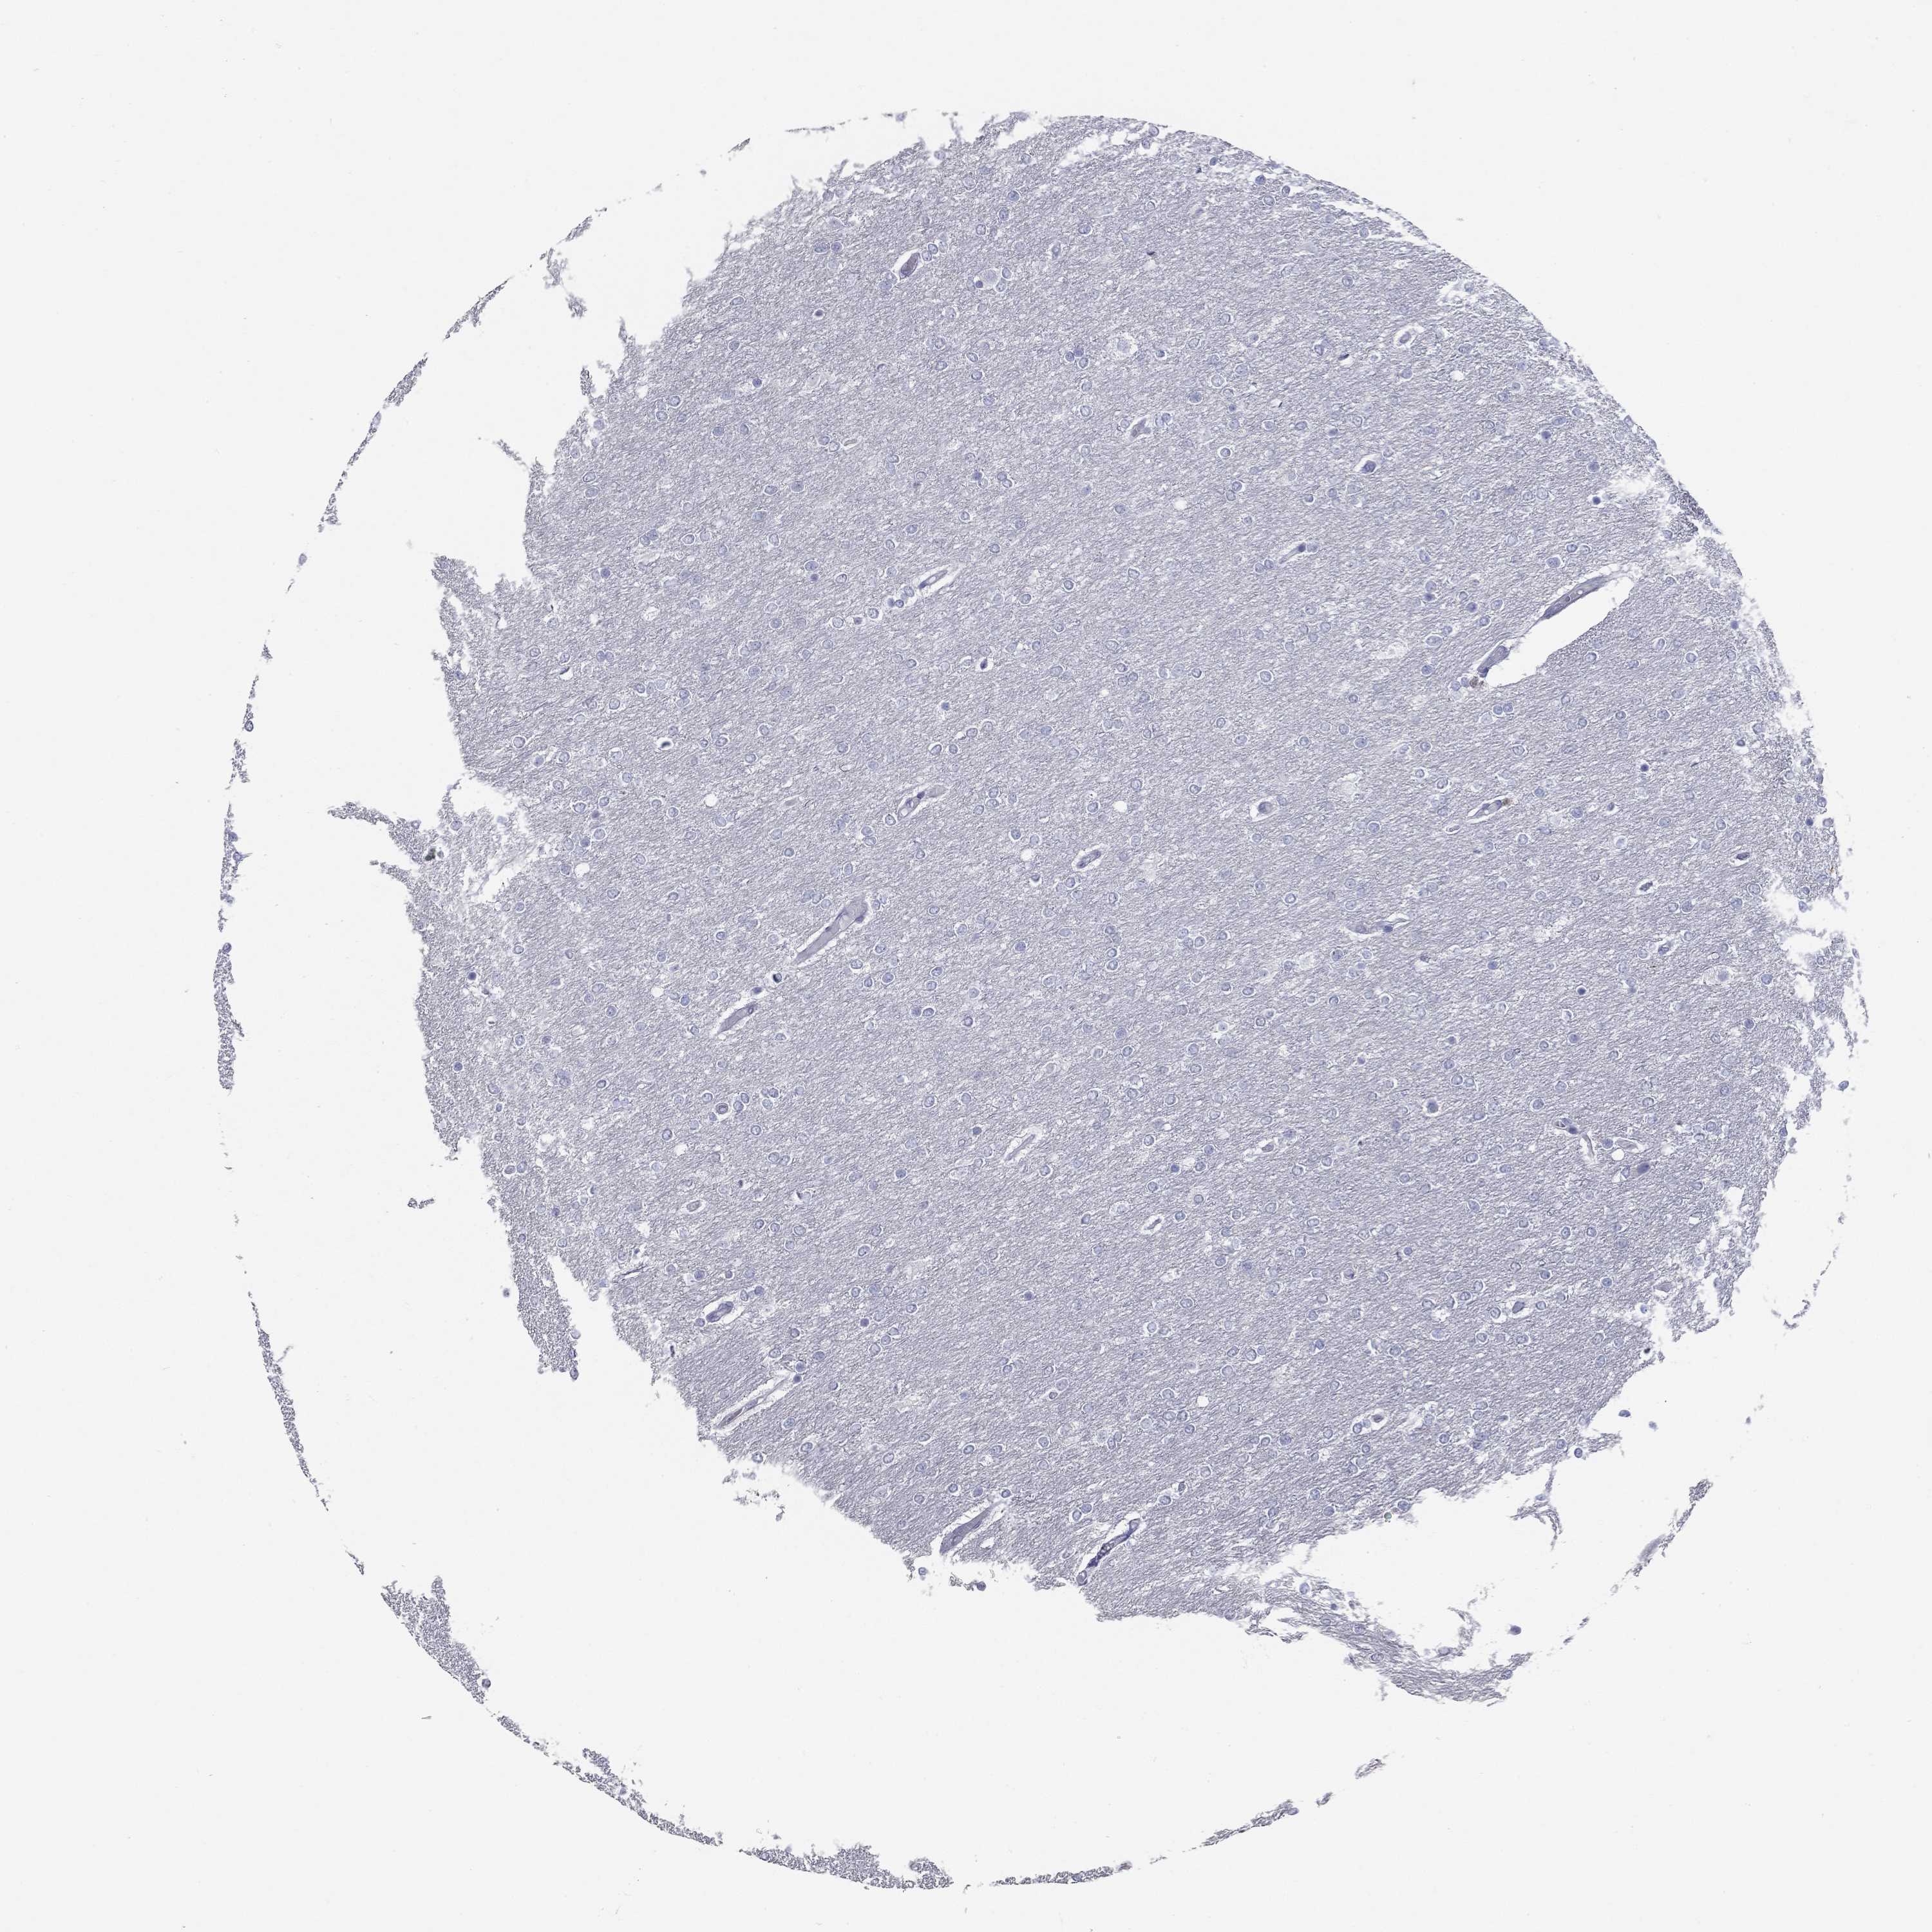

GLIOMA - Protein expressioni

A mouse-over function shows sample information and annotation data. Click on an image to view it in a full screen mode. Samples can be filtered based on level of antibody staining by selecting one or several of the following categories: high, medium, low and not detected. The assay and annotation is described here.

Note that samples used for immunohistochemistry by the Human Protein Atlas do not correspond to samples in the TCGA dataset.

Antibody stainingi

Antibody staining in the annotated cell types in the current human tissue is reported as not detected, low, medium, or high, based on conventional immunohistochemistry profiling in selected tissues. This score is based on the combination of the staining intensity and fraction of stained cells.

Each image is clickable and will lead to virtual microscopy that enables deeper exploration of all samples and also displays staining intensity scores, fraction scores and subcellular localization as well as patient and tissue information for each sample.

Antibody HPA014429

Staining

High

Medium

Low

Not detected

Intensity

Strong

Moderate

Weak

Negative

Quantity

>75%

75%-25%

<25%

None

Glioma, malignant, Low grade

Glioma, malignant, High grade

Glioma, malignant, NOS